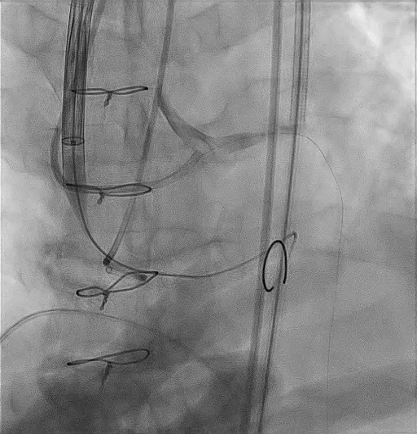

SEV 24 mm was chosen based on CT measurement and bifemoral access was obtained. Carotid filter was placed for cerebral protection.During resheathing of the valve there was sudden circulatory collapse. CPR started and left coronary catheterisation revealed occlusion of left main. Flow was established in LAD with immediate wiring and ballooning. Finally TAVR valve was deployed after LAD flow was established.LCX flow was then resolved and LM bifurcation PCI was done using crush technique Patient was finally discharged in hemodynamically stable condition.